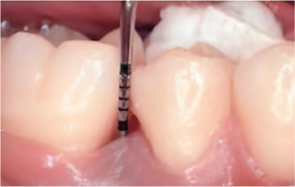

Emdogain Surgical Procedure

STEP 02

Scaling and Root Planing (SRP)

Before & After